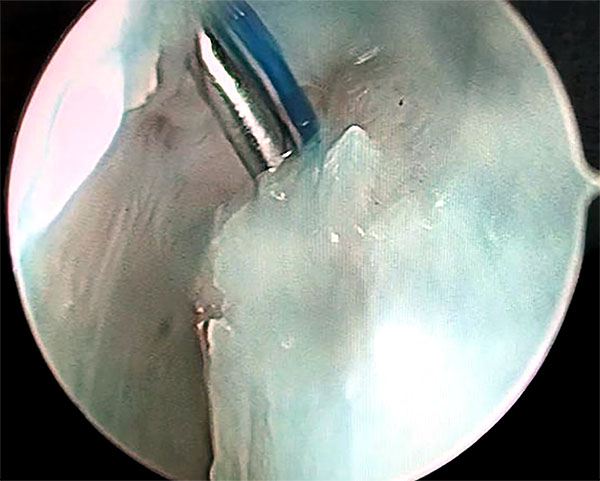

Luego por articulación radiocarpiana, se debrida y estimula el ligamento escafolunar; y si lo amerita realizamos radiofrecuencia del mismo previo a Capsulodesis. Terminado este paso, realizamos la técnica modificada de Mathoulin. Se realiza el pasaje de una sutura prolene 2.0 por medio de una aguja intramuscular desde la cápsula dorsal 1 cm proximal al portal 3/4 y 1 cm cubital (figs. 1 a 4).

Figuras 1 a 4: Muestran visión por portales 6R con ingreso de agujas con hilos desde capsulo hacia el ligamento escafolunar.

Se realiza visión por portal 6r y se pasa la aguja por la cápsula y uno de los sectores dañados del ligamento escafolunar hacia la articulación mediocarpiana donde se rescata la sutura y se retira por el portal MCR con visión MCU. Se repite este paso con otra aguja paralela a la primera que atraviese la cápsula y la otra parte del ligamento escafolunar dañada, y se rescata la sutura por articulación medio carpiana. Las 2 suturas rescatadas por mediocarpiano se anudan de forma simple, y se realiza el deslizamiento de los extremos de las suturas proximales con visión MCU, consiguiendo que el nudo quede anclado por mediocarpiano en el lig. Escafolunar (figs. 5 a 10).

Figuras 1 a 10: Muestran el ingreso de las agujas desde el portal radiocarpiano al mediocarpiano y el retiro de los hilos por el portal MCR con el nudo anclado en espacio mediocarpiano.